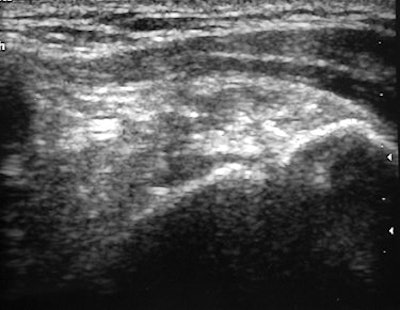

| A 39-year-old woman with calcific tendinitis for six months. Before treatment, longitudinal sonogram of supraspinatus tendon shows focus of calcification and acoustic shadow. |

According to the results, the suprasinatus tendon was involved in 57 of the 67 shoulders. In 83.6% of the cases, radiographs showed dense, homogenous, and well-defined calcifications. All calcifications were visible on sonography with 58.2% demonstrating a strong acoustic shadow. In terms of calcium extractions, the mean volume per patient was 0.4 mL with no calcium extracted in 25% of the subjects.